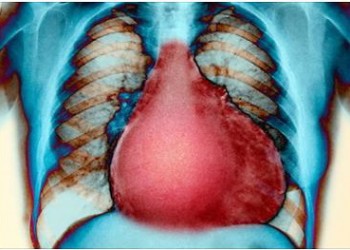

Cardiomiopatiile

Cardiomiopatiile sunt afec?iuni primare ale mu?chiului cardiac, cheap no rx care asociaz? o disfunc?ie cardiac?. Afect?rile miocardului datorate ischemiei, hipertensiunii arteriale, bolilor cardiace congenitale, valvulopatiilor ?i bolilor pulmonare cronice sunt incluse în categoria cardiomiopatiilor specifice.

• cardiomiopatia dilatativă (CMD): este cea mai frecventă formă de cardiomopatie, se caracterizează prin dilataţie ventriculară şi alterarea funcţiei sistolice, uneori mergând până la insuficienţă cardiacă congestivă.